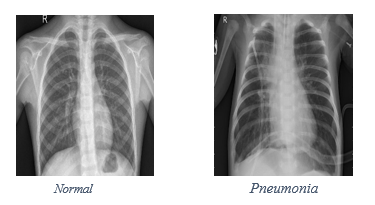

Chest X Ray Images Pneumonia Kaggle